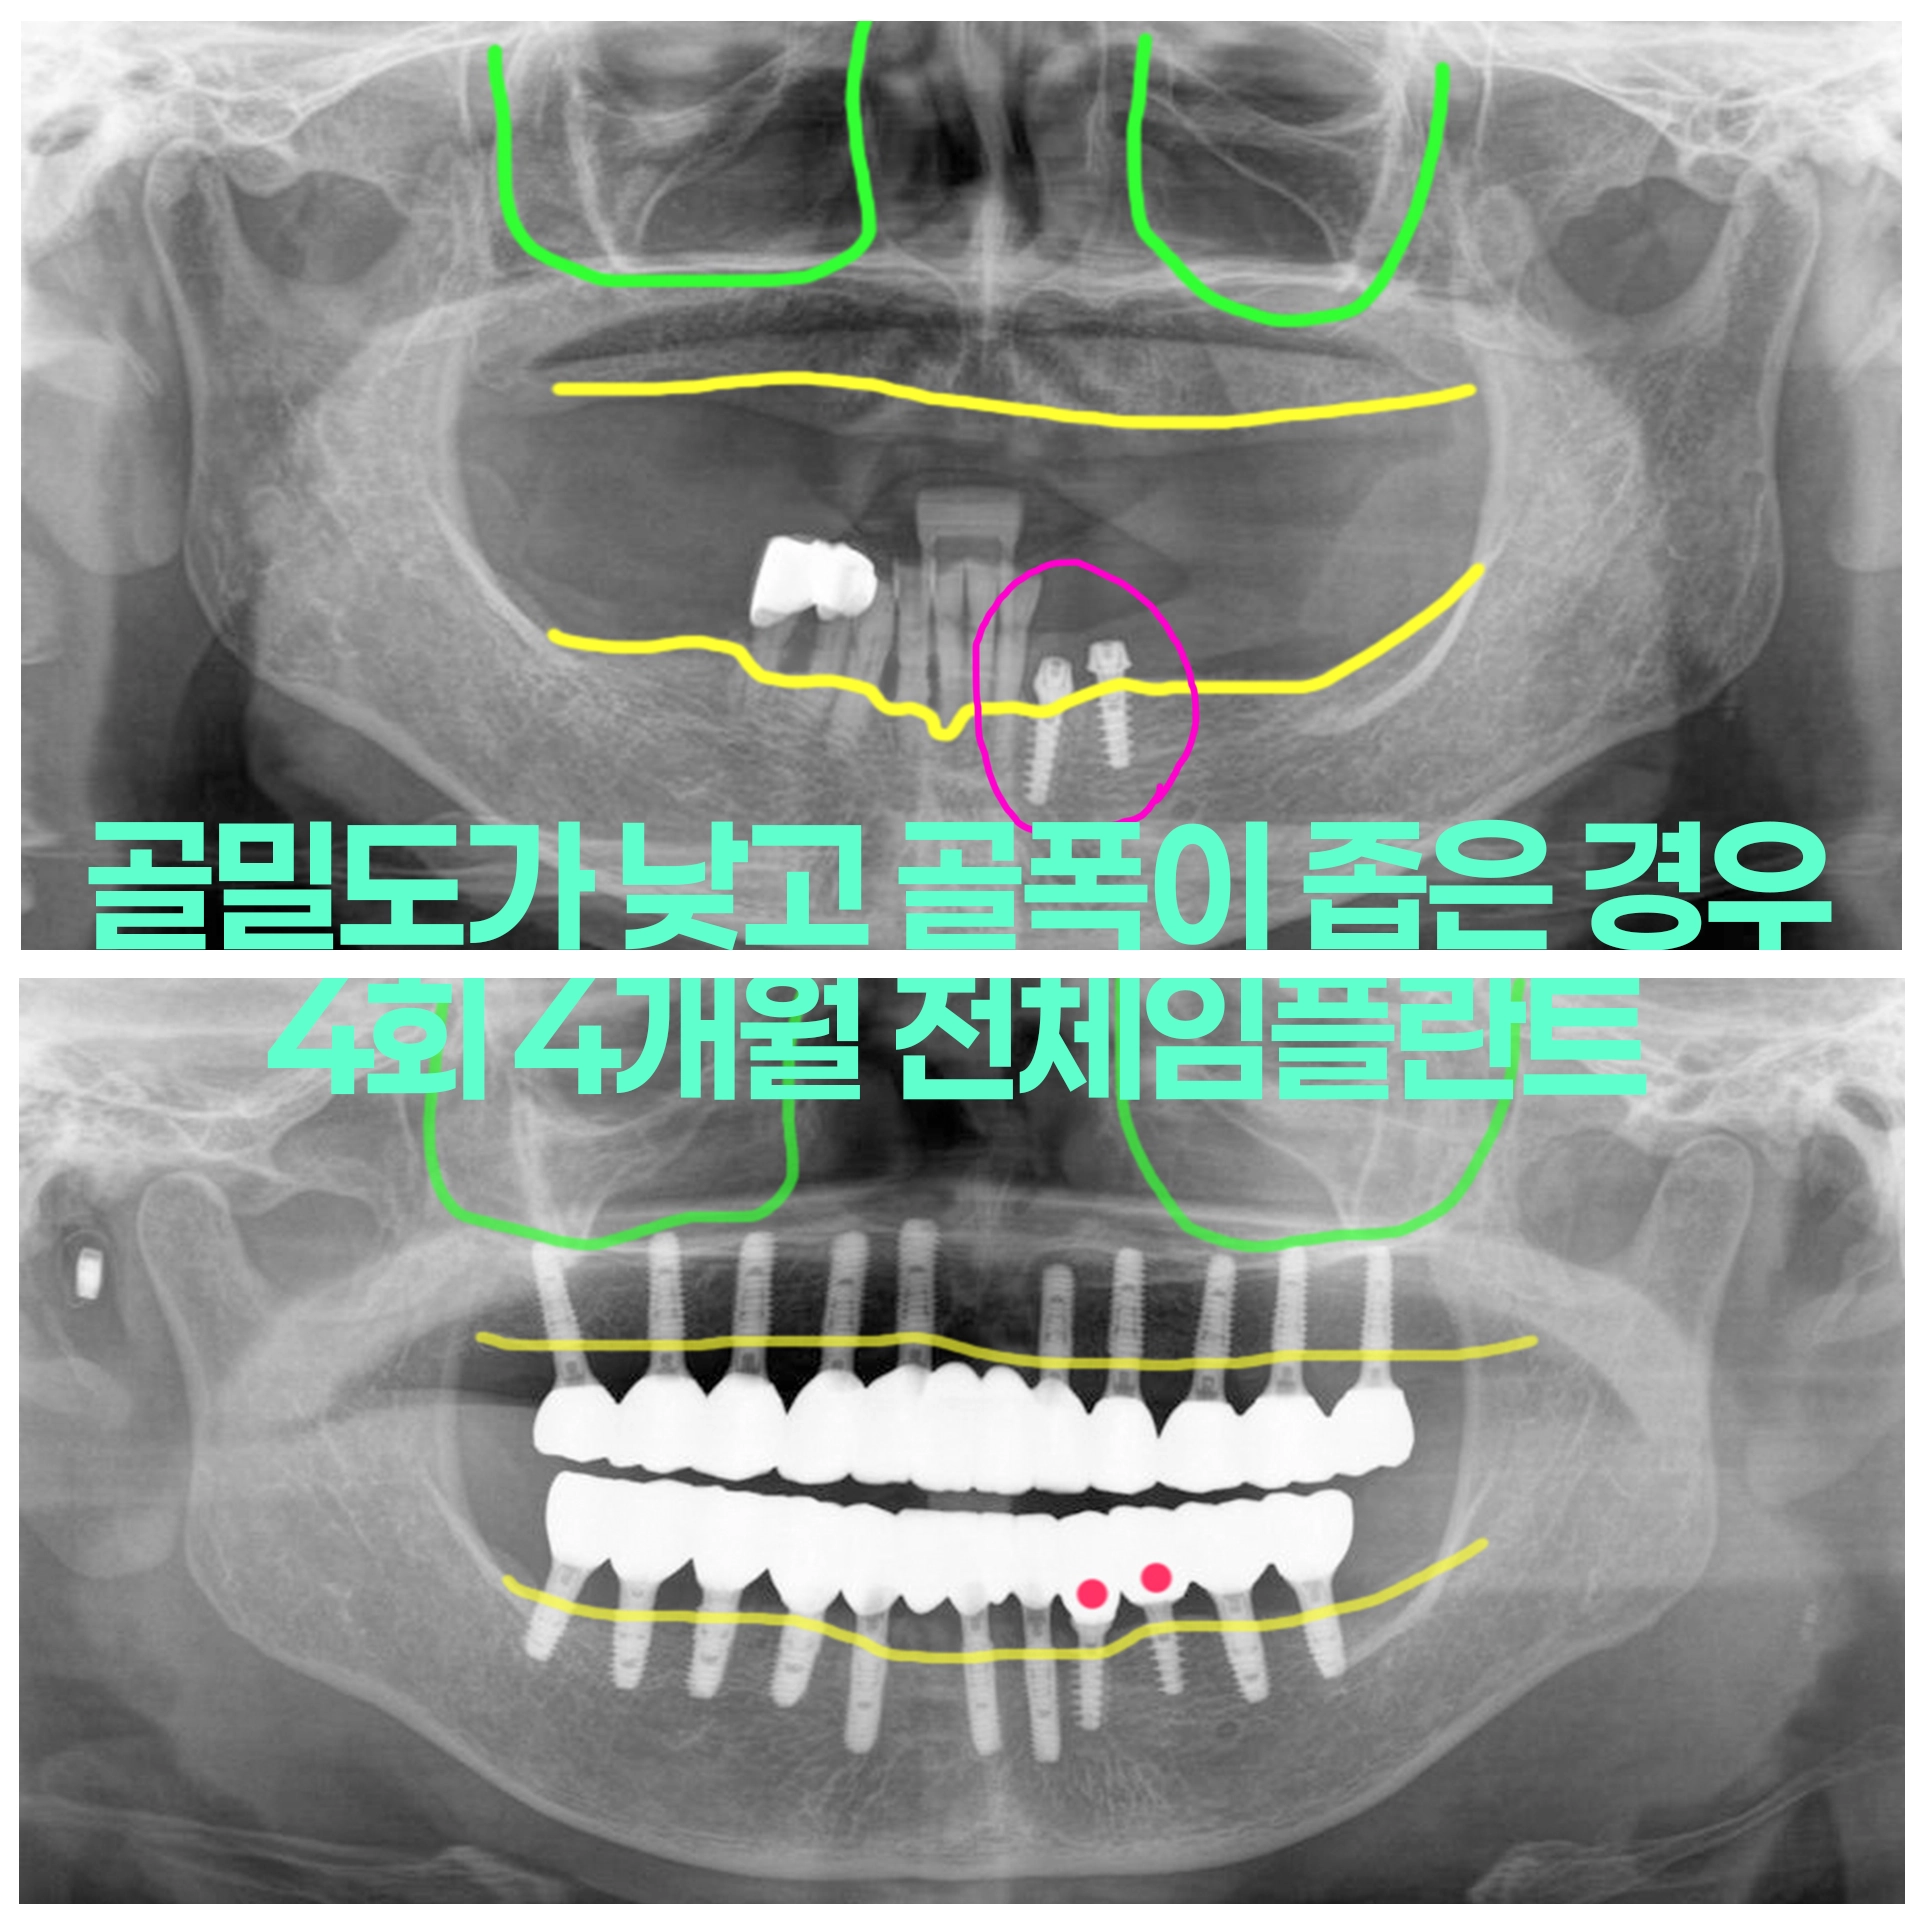

골다공증으로 골밀도가 낮은 경우 만성치주염(잇몸질환)으로 즉시하중 파워아치 전체임플란트